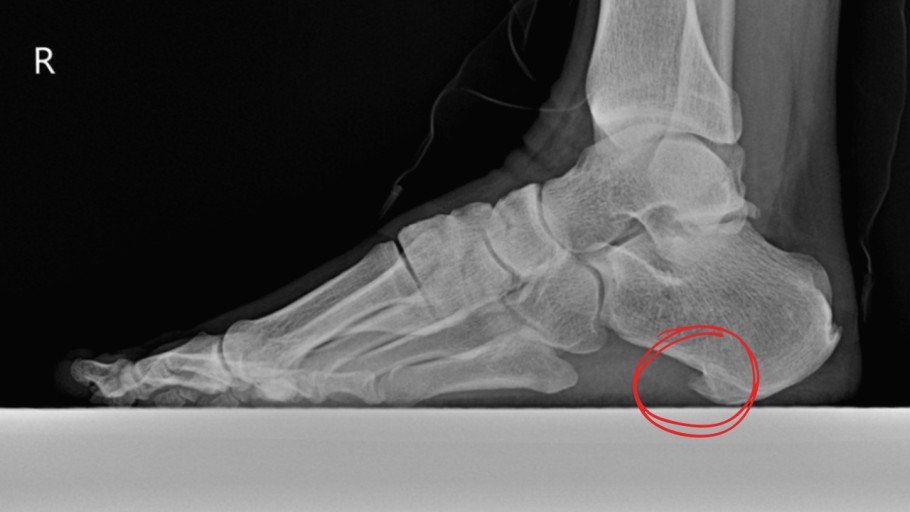

1. 족저근막염

가장 흔한 원인 중 하나로,

발바닥 아치 밑을 지탱하는 족저근막에 염증이 생긴 상태입니다.

특히 아침에 첫발 디딜 때 극심한 통증이 느껴지며,

걷다 보면 통증이 조금 완화되지만 반복적으로 악화됩니다.